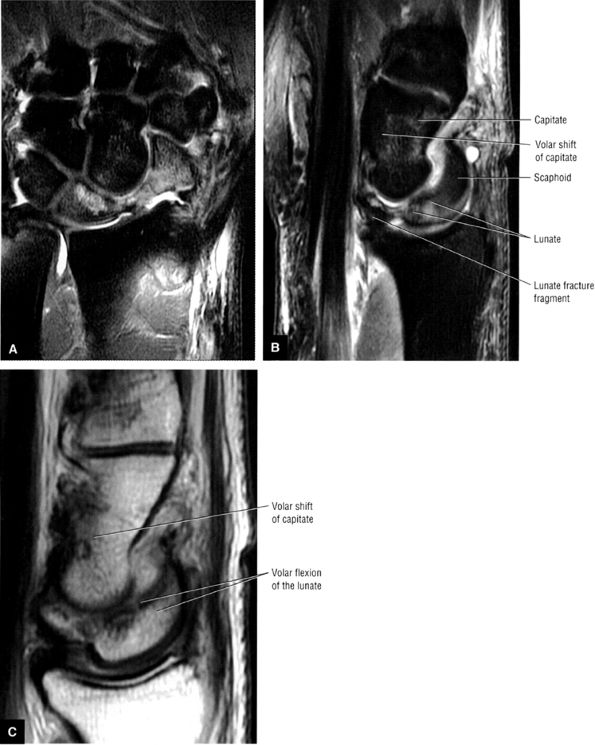

exceeds 30°. When DISI is present, the scapholunate ligament is evaluated for associated tears. The position of the scaphoid with respect to the rest of the carpus is also assessed. An anteriorly tipped or “flexed” scaphoid is an additional sign of DISI. When the lunate is tipped in a volar direction, with palmar translocation of the carpus, volar intercalated segmental instability (VISI) is suggested. VISI is associated with lunotriquetral ligament tears and dorsal extrinsic ligament injuries.

Compression forces transmitted by the capitate produce dorsal rotation or dorsiflexion of the lunate. Associated volar shift of the lunate maintains colinear alignment of the capitate and radius.

During lunate dorsiflexion, there is elevation of the distal pole of the scaphoid (i.e., scaphoid extension). Thus, in ulnar deviation, an extension torque predominates, and interaction at the triquetrohamate helicoid slope and proximal carpal row extension produces a physiologic DISI pattern.